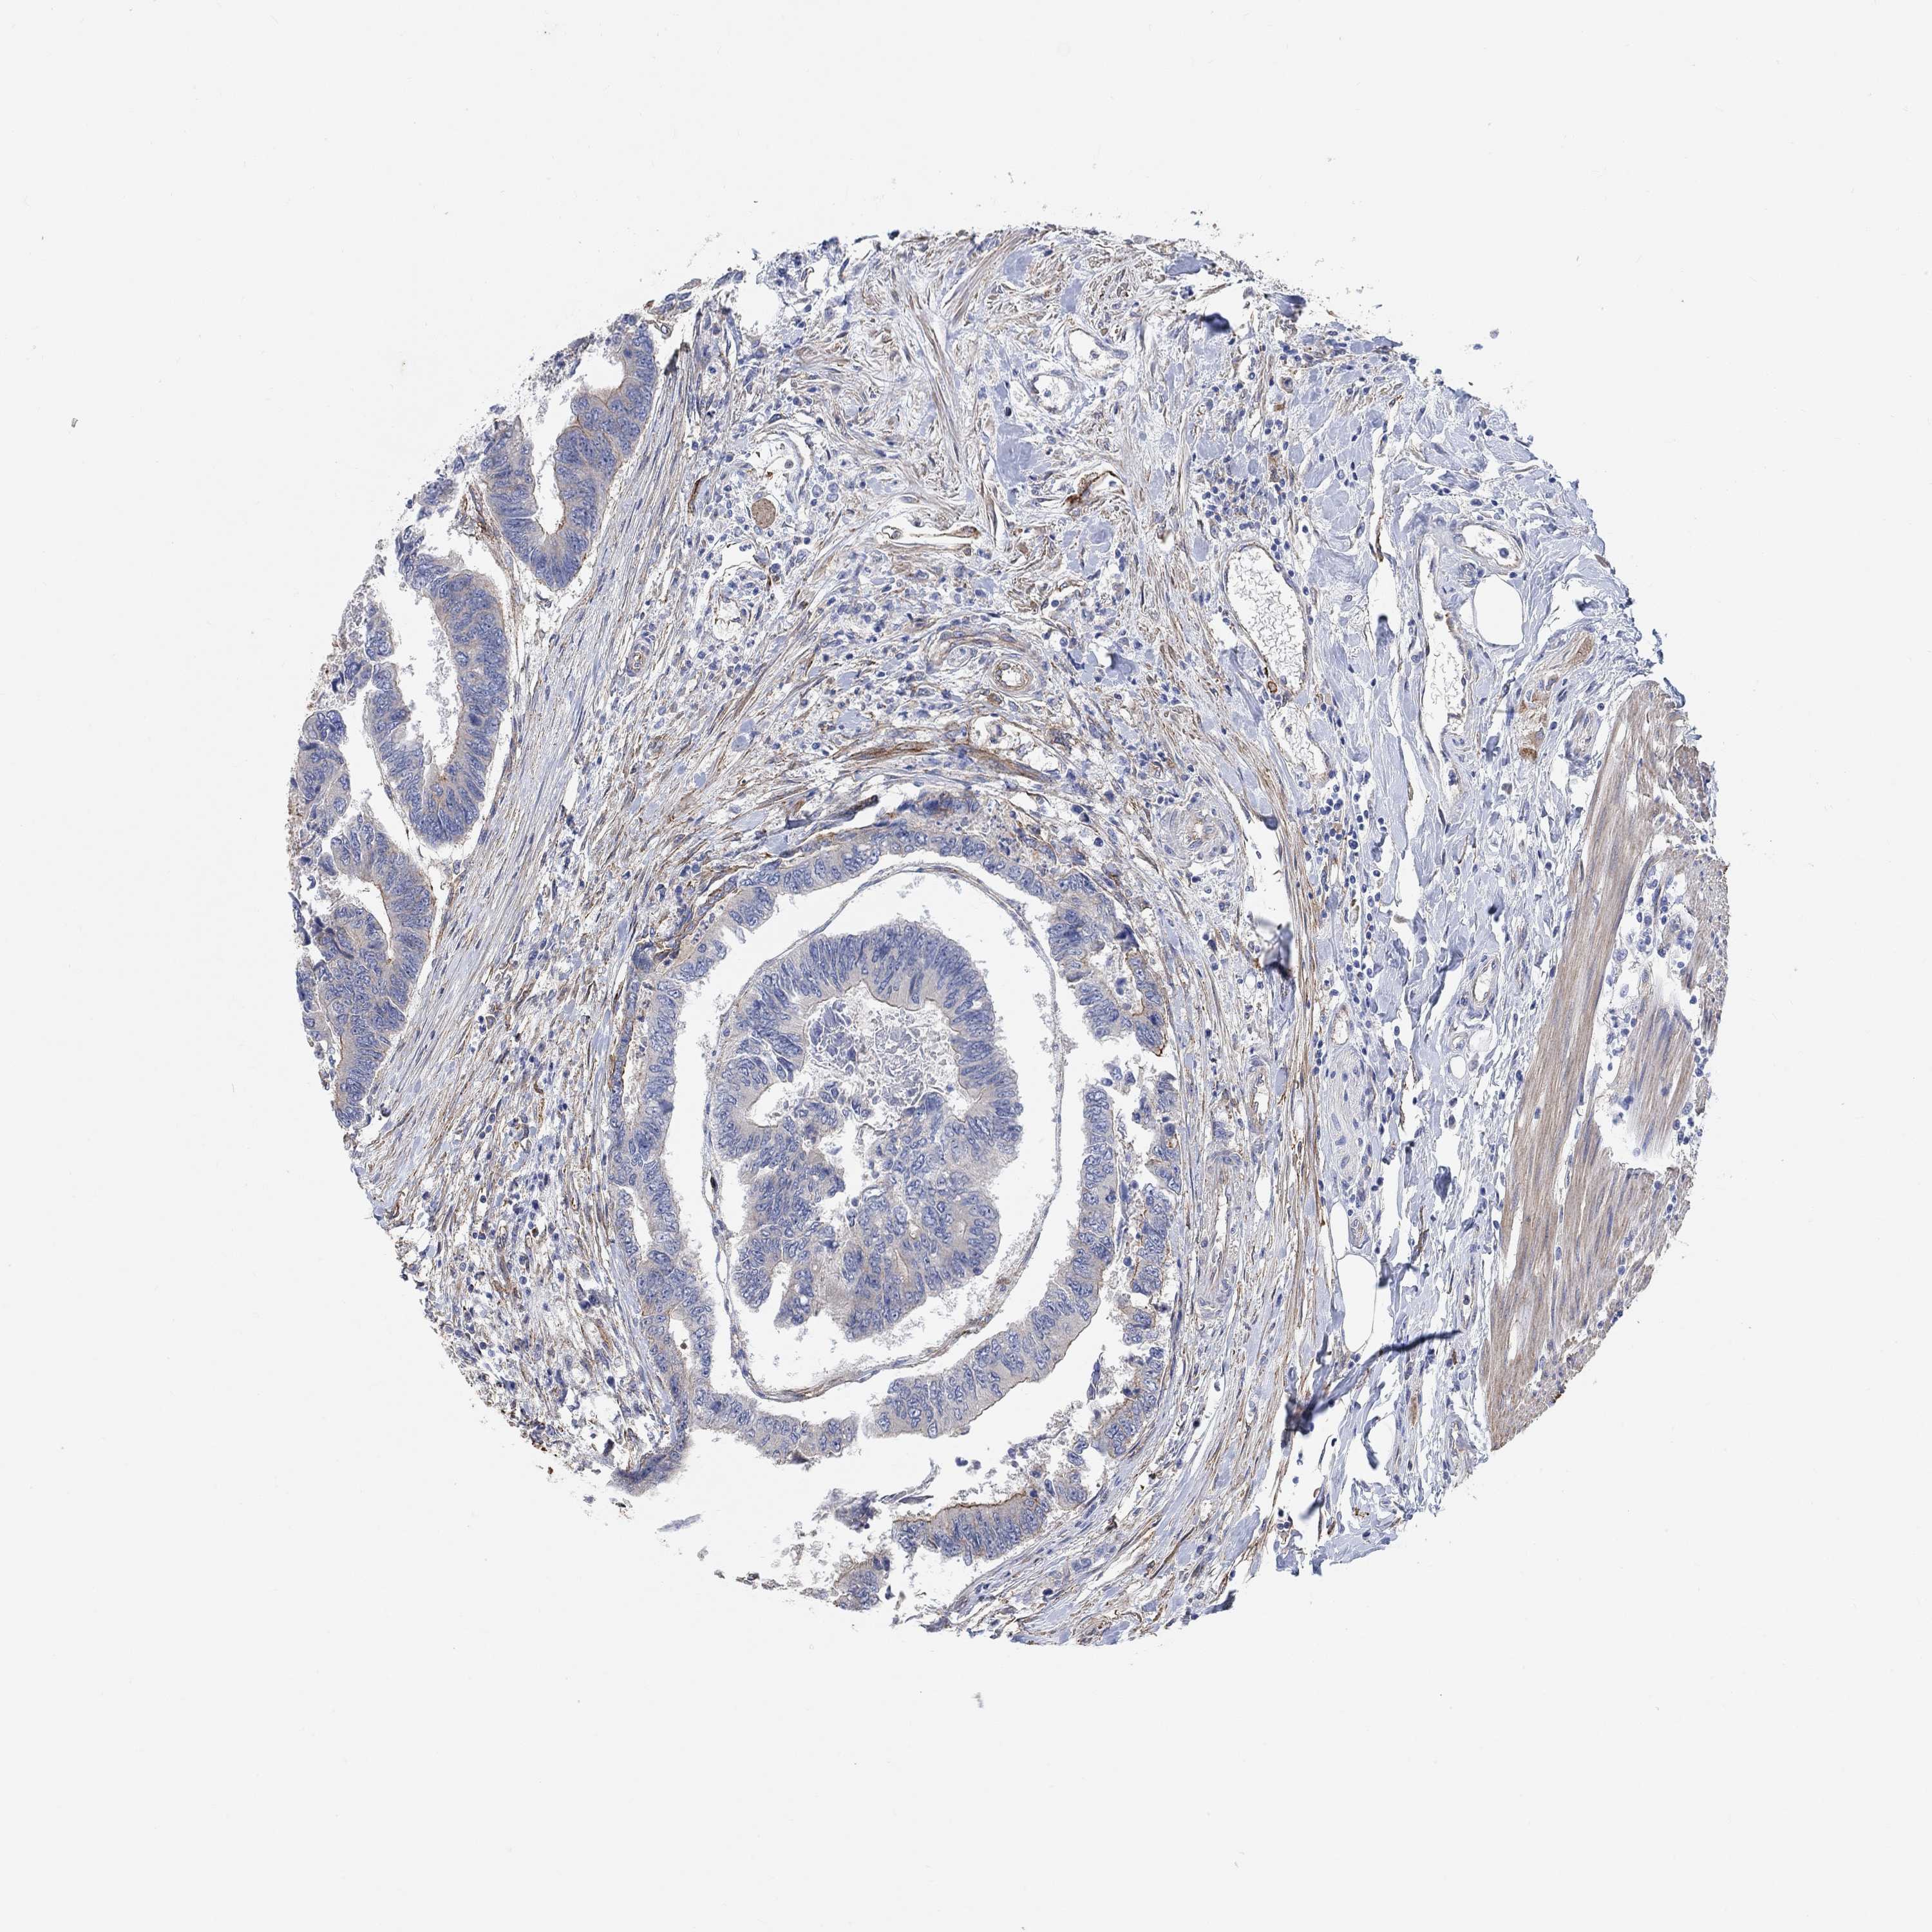

CANCER COLORECTAL CANCER Show tissue menu

Colorectal cancer

Colon adenocarcinoma